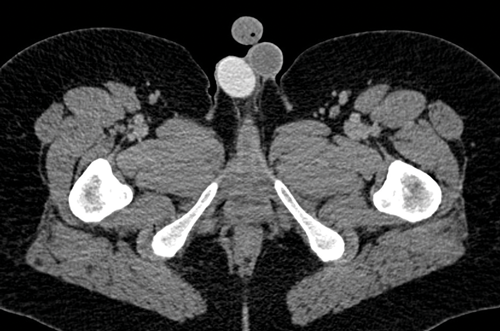

Figure 9. Axial CT shows a right sided testicular prosthesis which is of high attenuation due to the internal contents.

Testicular prosthesis

Testicular prosthesis can be inserted at the time of initial surgery, at a later date, or patients may decide not to have a prosthesis. The prosthesis can be seen on subsequent CT and is usually well defined and of high attenuation, due to the internal contents (Figure 9). A prosthesis on ultrasound has a very echogenic anterior border but dense posterior acoustic shadowing, and nothing can be seen behind the anterior border.